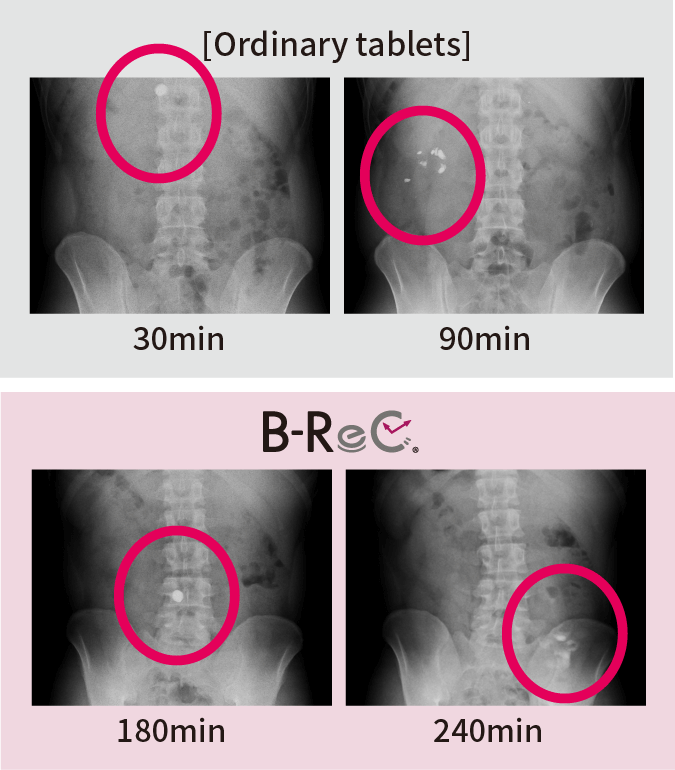

We confirmed the pharmacokinetic profile of ordinary tablets and B-ReC tablets. Ordinary tablets completely disintegrated within 90 minutes from the stomach to the duodenum, but the jejunum-disintegrating B-ReC tablets did not disintegrate in the upper small intestine (jejunum) even 180 minutes after ingestion, but in the middle small intestine after 240 minutes.

This proves that

the formulation can deliver the

functional ingredients

to the target site in the

digestive tract. -